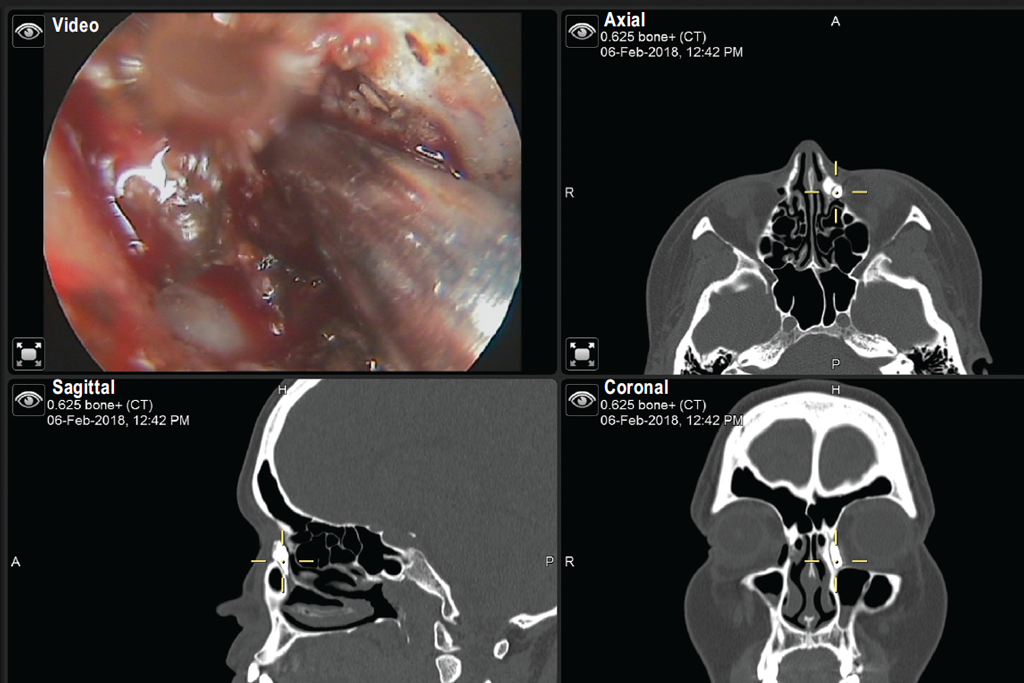

Surgical intervention (revision EELDCRS in 2018) was performed in an otorhinolaryngology clinic under general anesthesia with the navigation system and using a semiconductor laser with a wavelength of 970 nm in the continuous contact mode (Fig. 2).

The cicatricial tissue was excised in the projection of the bone window. Then, the remnants of the bone mass were removed with a drill. At the final stage, a bicanalicular silicone stent was placed through the upper and lower lacrimal openings, with subsequent fixation of its ends with knots in the nasal cavity. At each stage, the location of the instrument relative to the structures of the nasal cavity was monitored using a navigation station (Fig. 3).

Fig. 3. The image from navigation station showing X-ray and endoscopic view of nasal cavity and lacrimal pathways

Рис. 3. Изображение с навигационной станции, показывающее рентгенологическую и эндоскопическую картину полости носа и слезоотводящих путей

The navigation equipment was used for accurate determination of the structures of the nasal cavity and lacrimal passages under conditions of altered anatomy, and this contributed to accurate planning and safe performance of endoscopic intervention.